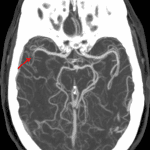

- Focal hyperdensity associated with an M2 branch of the right MCA

- Acute right MCA territory infarct (dense vessel sign)

Focal hyperdensity associated with an M2 branch of the right MCA concerning for age-indeterminate thrombus. Consider CTA for further evaluation. No definite CT findings of infarct; however, MRI is more sensitive for acute ischemia.